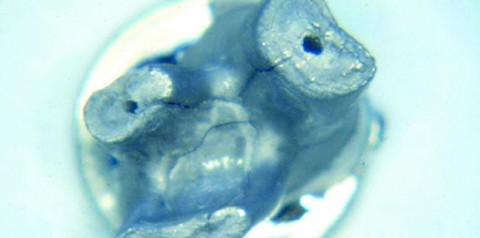

Eine weitere Verbindung von Zahnhalteapparat und Pulpa stellen die akzessorischen Kanäle dar, die in den lateralen Wurzelbereich oder in den Furkationsbereich münden.5 Gelangen bakterielle Produkte und Antigene hierbei in den Furkationsereich, so kann eine interradikuläre Osteolyse entstehen, die röntgenologisch zu sehen ist. Auch wenn nicht alle Pulpa-Desmodont-Kanäle vollständig durchgängig sind, so stellen ihre Öffnungen im Bereich der Furkation bakterielle Rückzugsmöglichkeiten dar (Abb. 1 und 2). Weiterhin sind laterale Kanäle bekannt, die vor allem im apikalen Wurzeldrittel oberer Molaren auftreten6 (Abb. 3 und 4) – hier kann die Infektion zu einer lateralen Osteolyse führen –, während Dentinkanäle vor allem an der Schmelz-Zement Grenze vorkommen. Die Vielzahl der kommunizierenden Wege liegt im gemeinsamen entwicklungsgeschichtlichen Ursprung von Parodont und Endodont begründet. Bei den parodontalen und auch endodontalen bakteriellen Infektionen spricht man von einer Mischinfektion. Zu den am häufigsten gefundenen Keimen gehören Porphyromonas gingivalis, Tannerella forsythensis, Fusobakterien und Spirochäten.8